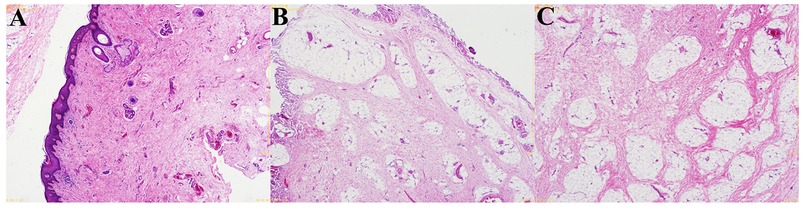

Background: Pediatric penile hamartoma is extremely rare. Preoperative imaging often cannot definitively characterize the lesion, and histopathology remains the diagnostic gold standard. We report a child with penile hamartoma and torsion, discuss management, and compare outcomes with the literature. Methods: We retrospectively analyzed the clinical presentation, imaging, intraoperative findings, and pathology. Relevant reports were reviewed for comparison. Results: Complete excision of a ventral hamartomatous appendage plus circumcision and release of a fibrous tethering band achieved immediate torsion correction in a single stage. Histopathology showed stratified squamous epithelium with proliferative fibrous and adipose tissue containing nerve bundles, ganglion cells, and focal smooth muscle— consistent with hamartoma. Recovery was uneventful; at 12 months no recurrence was observed. Conclusion: Etiology‑targeted, one‑stage correction—degloving (circumcision), release of tethering bands, complete lesion excision, and simultaneous torsion repair—can be safe and effective. Long‑term follow‑up is advised.